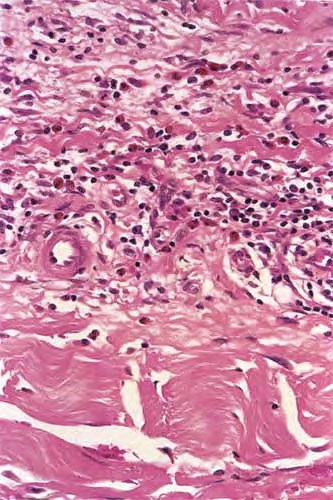

Histopathology

. A deep wedge biopsy to skeletal muscle including fascia is essential to making the diagnosis of eosinophilic fasciitis. The fascia is markedly thickened, appears homogeneous, and is permeated by a mononuclear inflammatory infiltrate . In some instances the infiltrate in the fascia contains an admixture of eosinophils . The underlying skeletal muscle in some cases shows myofiber degeneration, severe inflammation with a component of eosinophils, and focal scarring; in other cases, however, it is not involved.

In most cases the adipose tissue shows no significant changes, except that the fibrous septa separating deeply located fat lobules are thicker, paler staining, and more homogeneous and hyalinized than normal dermal connective tissue. In other cases, however, the collagen in the lower reticular dermis appears pale and homogeneous, and the entire subcutaneous fat is replaced by horizontally oriented, thick, homogeneous collagen containing only few fibroblasts and merging with the fascia